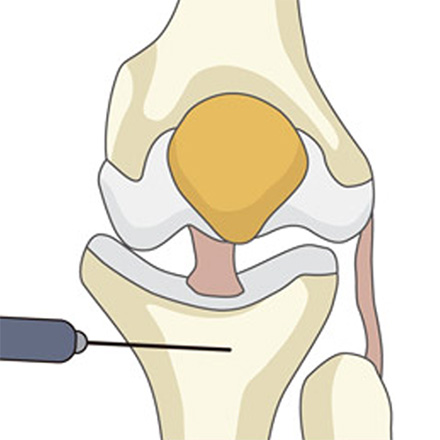

03

벌려진 공간에 인공뼈를 넣어 틀어져 있던 다리 축을 정상 각도로 바로잡습니다.

-

04

바로잡은 각도가 잘 유지되도록 금속 플레이트와 나사로 단단히 고정합니다.